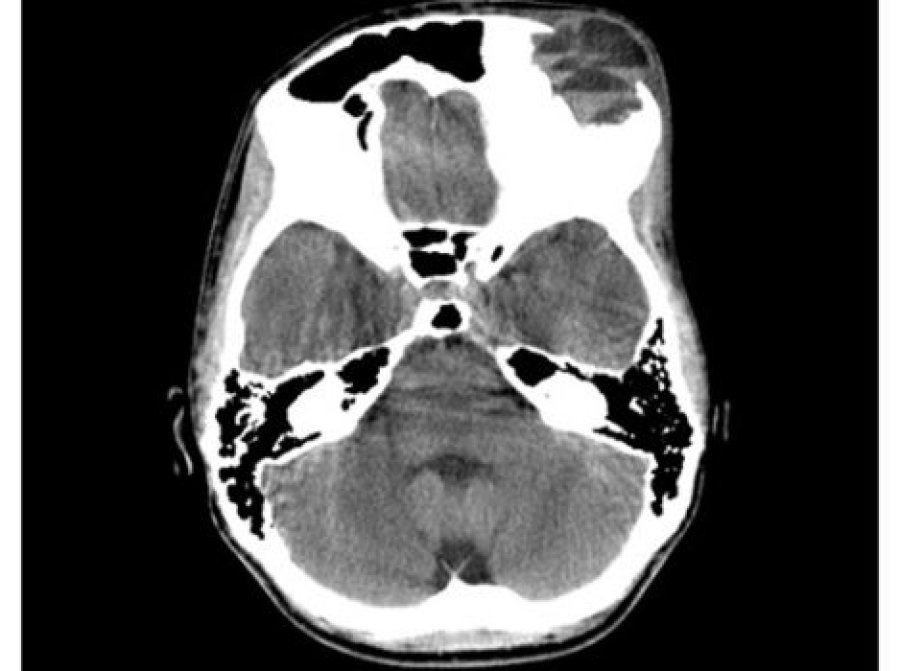

Learn MoreHaemorrhagic Vascular Disease

Haemorrhagic stroke, subarachnoid haemorrhage and vascular anomalies

Learn MoreHydrocephalus and CSF

Hydrocephalus, chiari malformations and syringomyelia in adults and children